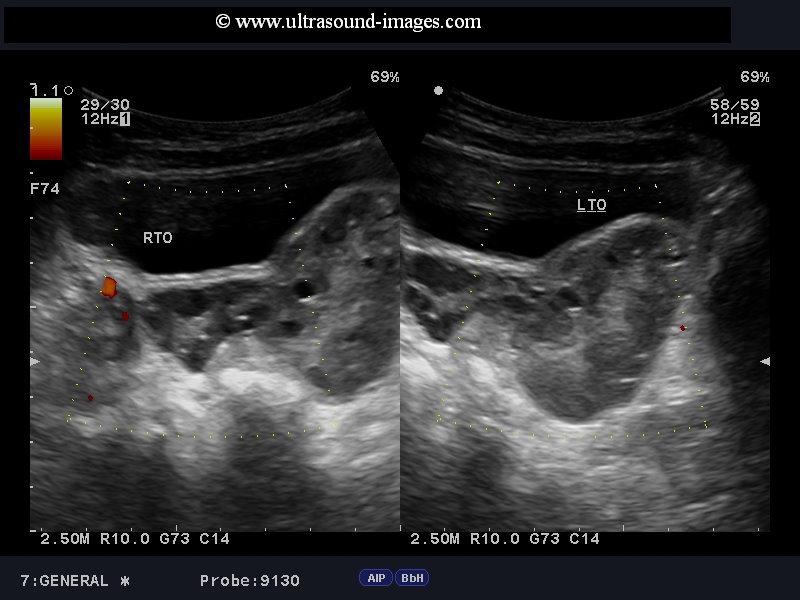

torsion of ovary or ovarian torsion

Case-2:

Case-1 (top):This young girl (6 years age) had severe left pelvic pain. Ultrasound images show an enlarged left ovary with lack of significant blood flow on power Doppler imaging. The right ovary appeared normal. These ultrasound images suggest torsion of the left ovary. This was surgically confirmed, with the left ovary seen to be gangrenous. The normal right ovary is seen as a pink healthy organ (see snapshot) compared to the gangrenous left ovary. These images of torsion of ovary are courtesy of Dr. Jaydeep Gandhi, MD, India.

Case-2: (lower set of images) also shows torsion of Rt. ovary with swollen edematous ovary with marked increase in ovarian volume. Absence of flow signals on color Doppler further confirms the diagnosis of Rt. ovarian torsion.

(2nd set of images- case -2): courtesy of Dr. Moin Kamran, MD.